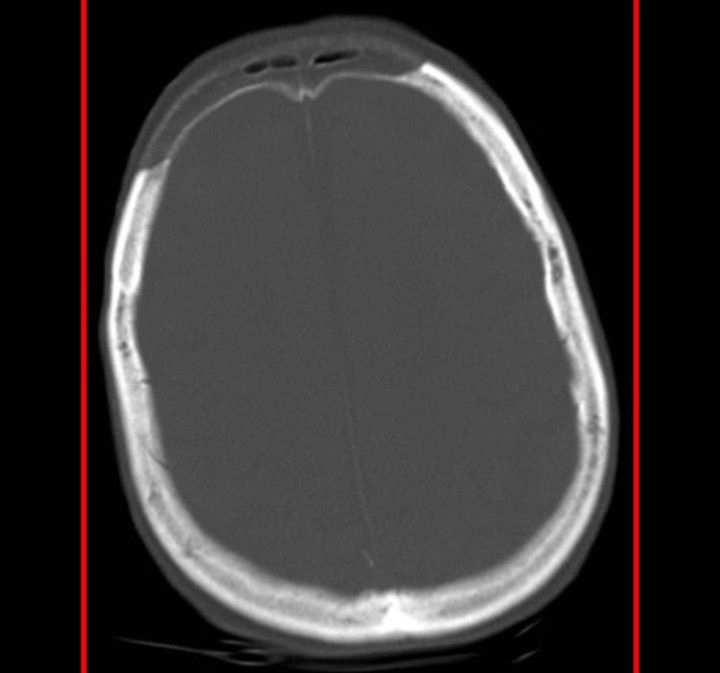

Osteoporosis circumscripta cranii refers to discrete radiolucent regions of the skull on plain radiographs. It is due to the extensive loss of bone density (lysis) involving the bilateral parietal and occipital bones, and the right temporal bone. The appearance is characteristic of the lytic phase of Paget disease and is often referred to as osteoporosis circumscripta. Credits: https://www.instagram.com/p/CQs2gSNL2lq/?utm_medium=copy_link